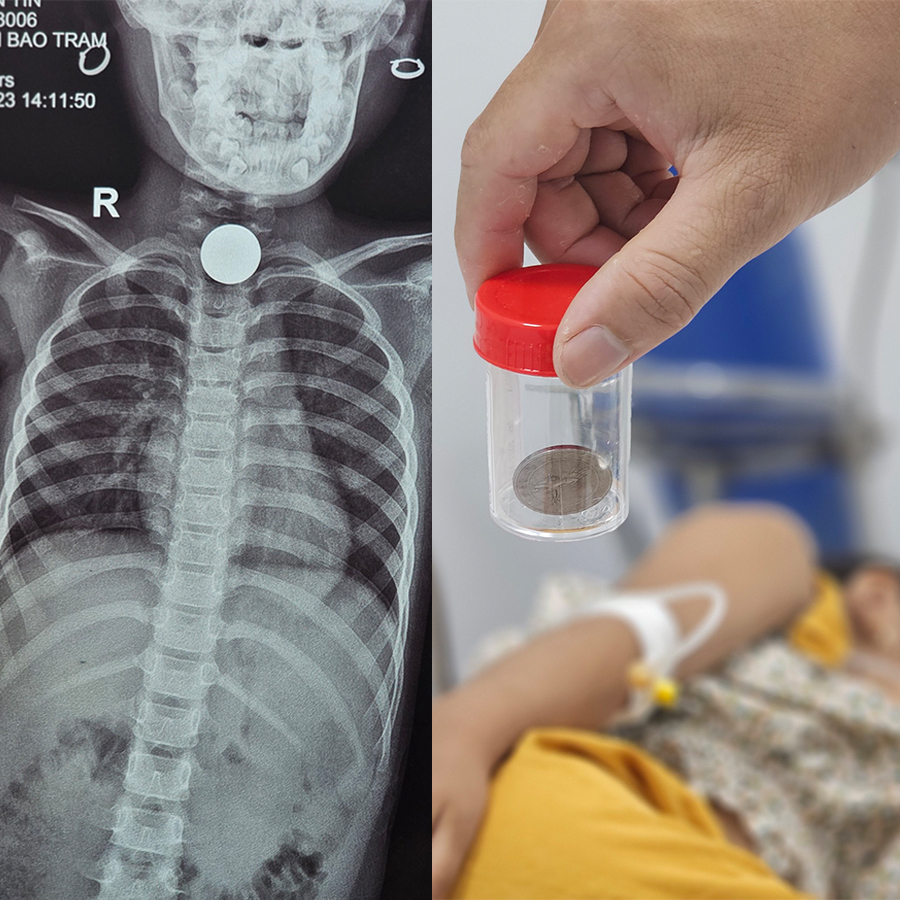

Theo lời người nhà kể lại, trước khi nhập viện 4 giờ, bé T chơi đồ chơi ở nhà và ngậm một đồng xu rồi đi ngủ. Khoảng 15p sau thì bé chạy ra kêu đau, tức ngực và kể cho bố mẹ. Bố mẹ đưa bé đến cơ sở y tế gần nhà chụp x quang phát hiện có dị vật hình tròn mắc ở thực quản nên đã đưa bé đến Bệnh viện 22-12.

Sau khi tiếp nhận bệnh nhân nhi, các bác sĩ đã tiến hành gây mê và nội soi can thiệp gắp dị vật. Sau chưa đầy 10 phút thực hiện thủ thuật, ekip nội soi do Bs.CKII Cao Nguyên Đính – Trưởng khoa Nội soi tiêu hóa Bệnh viện 22-12 đã gắp thành công một đồng xu kim loại có đường kính 2cm ra khỏi thực quản của bé. 25 phút sau nội soi, bệnh nhân đã tỉnh táo hoàn toàn, hết đau ngực, hết khó thở, không còn dấu hiệu nuốt vướng, nghẹn và đã được về nhà.